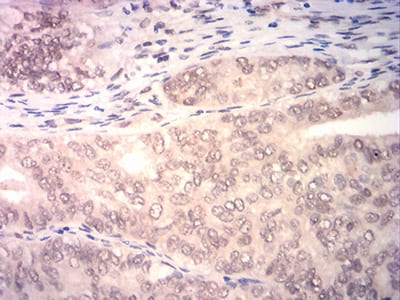

分类: 科研抗体货号: 31838别名: HL-2; HBXBP; ASGPR2; ASGP-R2; CLEC4H2应用: IHC,FCM反应种属: Human